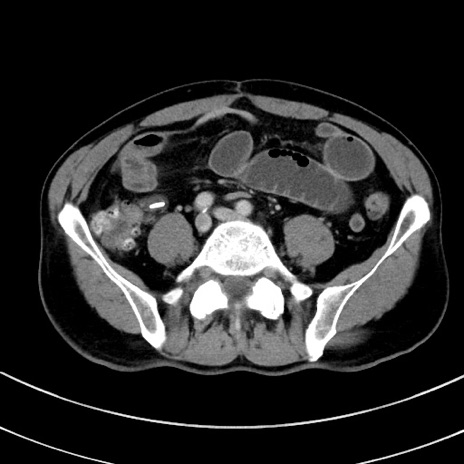

症例8(横断像)

【症例】 60歳代男性

【主訴】 黒色吐物

【現病歴】 4日前から嘔気自覚、2日前の朝食後にも嘔気あり、自分で手で嘔吐反射起こし嘔吐したところ血が混ざっていたため受診。

【既往歴】 5年前汎発性腹膜炎を伴う急性虫垂炎で手術、高血圧、前立腺肥大症、高脂血症

【身体所見】 腹部正中に手術癩痕あり 腹部平坦・軟圧痛なし膨満感あり

【データ】WBC 8400、CRP 4.54